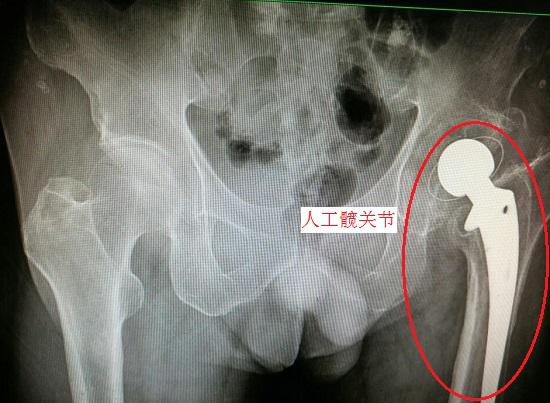

髖關節置換術

股骨頸骨折後的關節置換,需要對股骨頭及斷裂的股骨頸進行人工假體置換,並在置換後實施長期的康復訓練,預後情況與患者傷前髖關節狀況、手術技術、術後康復治療水平、患者配合度等因素高度相關,需要進行較大範圍的組織切割和結構改造,對於普通的股骨頸骨折並不適用。

股骨頸骨折後髖關節置換術的適應證主要有:1、存在退行性骨關節炎;2、股骨頭壞死、缺血;3、髖臼發育不良並引發髖關節炎的;4、類風溼關節炎和強直性關節炎使髖關節受累;5、骨質差的老年患者;6、髖關節發育不良者並引發顯著症狀的;7、髖關節的持續感染、髖關節腫瘤等髖部病變;8、其他病變且非手術治療無效者。